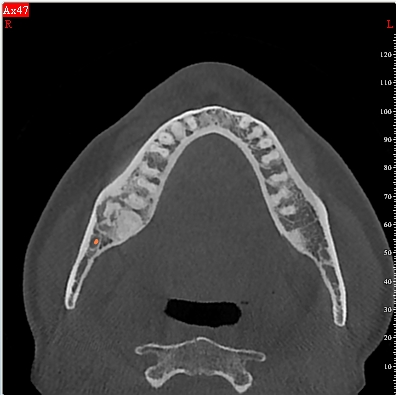

- Στο τρίτο στάδιο είναι έντονα ακτινοσκιερή αλλοίωση που συνήθως περιβάλλεται από διαυγαστική ζώνη.